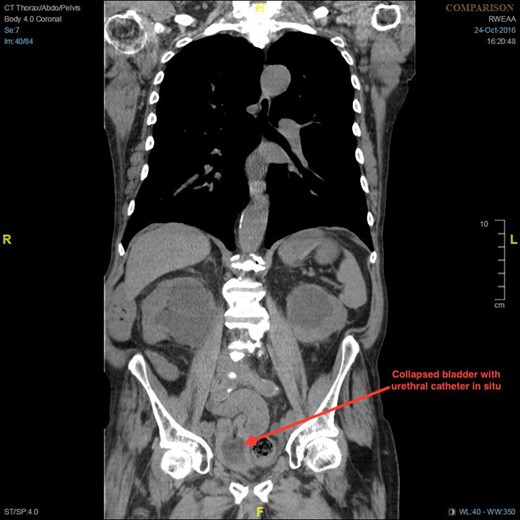

Non-contrast CT of the chest, abdomen and pelvis was performed on admission looking for malignancy considering his visible haematuria and significant unintentional weight loss. This demonstrated severe bilateral hydronephrosis and hydroureter, which was more prominent on the left side (Figs 2–4). The left ureter tapered in the pelvis and neither the bladder nor either ureter was seen in the inguinal canal and a large, left-sided inguinoscrotal hernia was seen containing distal colon. Bilateral loss of renal cortical thickness, a potassium of 6.0 mmol/L and an eGFR of 9 mL/min was suggestive of chronically obstructed kidneys.

Coronal section of CT demonstrating bilateral hydronephrosis and collapsed bladder with urethral catheter in situ.